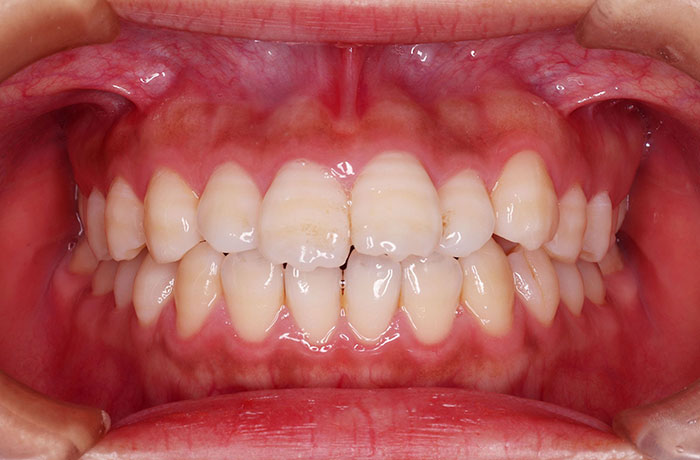

治療前

before

患者の症状 叢生、正中のずれ、上顎左右側切歯の口蓋側転位(交叉咬合)

治療方法 非抜歯で、マウスピース型カスタムメイド矯正歯科装置(インビザライン)による矯正

歯列弓を拡大することで非抜歯を可能にしました。

治療結果 側切歯の交叉咬合は解消、上下正中のずれも改善し咬み合わせが良くなりました。